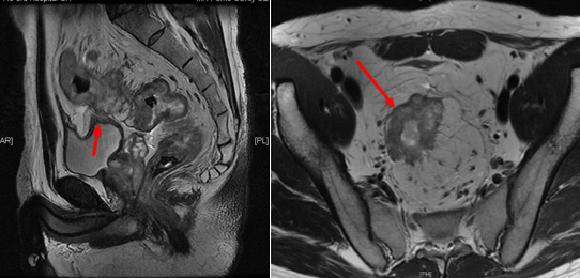

图1 核磁共振检查可见直肠及乙状结肠巨大肿瘤,与膀胱关系密切(T4期)(左图箭头);核磁共振检查可见肿瘤侵出直肠系膜(右图箭头)并伴有多发系膜淋巴结转移(N+)